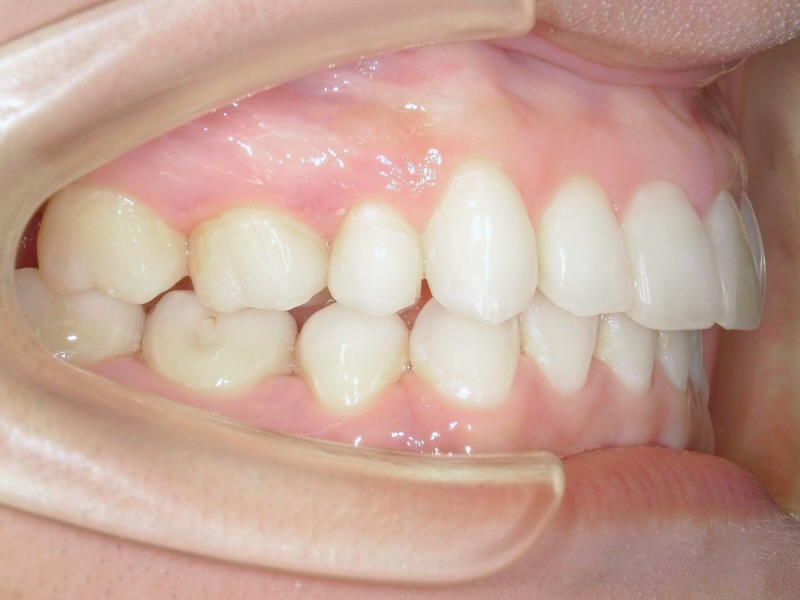

10代、女性、ワイヤー

| 施術内容 | 主訴:上下前歯でこぼこ。なるべく抜きたくない。 詳細:ワイヤー矯正での歯並び改善 詳細:ワイヤー矯正での歯並び改善 歯肉炎リスクあるため、今後は後戻りのチェックとともに歯肉炎管理もしていきます。 |

| 治療期間 | 12ヶ月(2/6現在 治療終了) |

| 費用 | ワイヤー矯正 60万円(税込660,000円) |